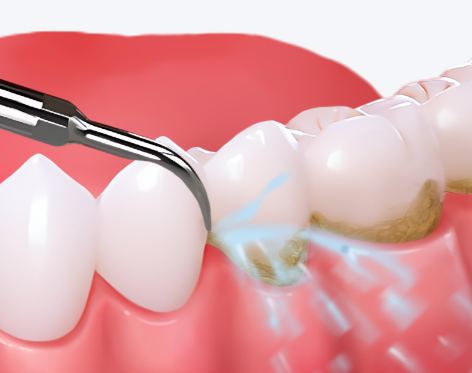

误吞少量洗牙水无需过度紧张,可先做应急处理:10分钟内用温清水漱口3-5次清理口腔残留,再喝200-300ml35-40℃温白开稀释代谢,轻微不适可用淡盐水漱口。正规口腔机构的洗牙水多为低浓度抑菌液或生理盐水,少量误吞(通常不足50ml)对健康人群无明显伤害,仅肠胃病患者可能短暂不适,1-2天可自行缓解。缓解可喝温牛奶、小米粥护黏膜,避免辛辣过烫食物,做好口腔护理并适量补水。若在非正规机构洗牙、误吞量大、出现严重过敏或特殊人群不适,需及时就医,建议选正规机构并配合操作减少误吞。